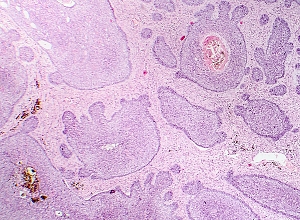

Participants applied remetinostat gel to their tumours three times per day for six weeks. After eight weeks, any remaining tumour was surgically removed and examined histologically.

Of the 33 tumours included in the final analysis, 69.7% responded to the topical treatment, with 17 complete responses and six partial responses. On average, tumour diameter decreased by 62.3%, and tumour area decreased by 71.5%.

Responses were observed across multiple BCC subtypes: there was a 100% response rate among the six superficial BCC tumours in the analysis (five complete responses, one partial response), 68.2% response rate among 22 nodular BCCs (10 complete responses, five partial responses), and 66.7% among three infiltrative BCCs (two complete responses). No responses were observed in the two tumors of micronodular subtype.

Thirty-three per-protocol tumours from 25 participants were included in the analysis. The overall response rate, defined as the proportion of tumors achieving more than 30% decrease in the longest diameter from baseline to week 8, was 69.7% [90% confidence interval (CI), 54%–82.5%]. On pathologic examination, 54.8% of tumours demonstrated complete resolution.